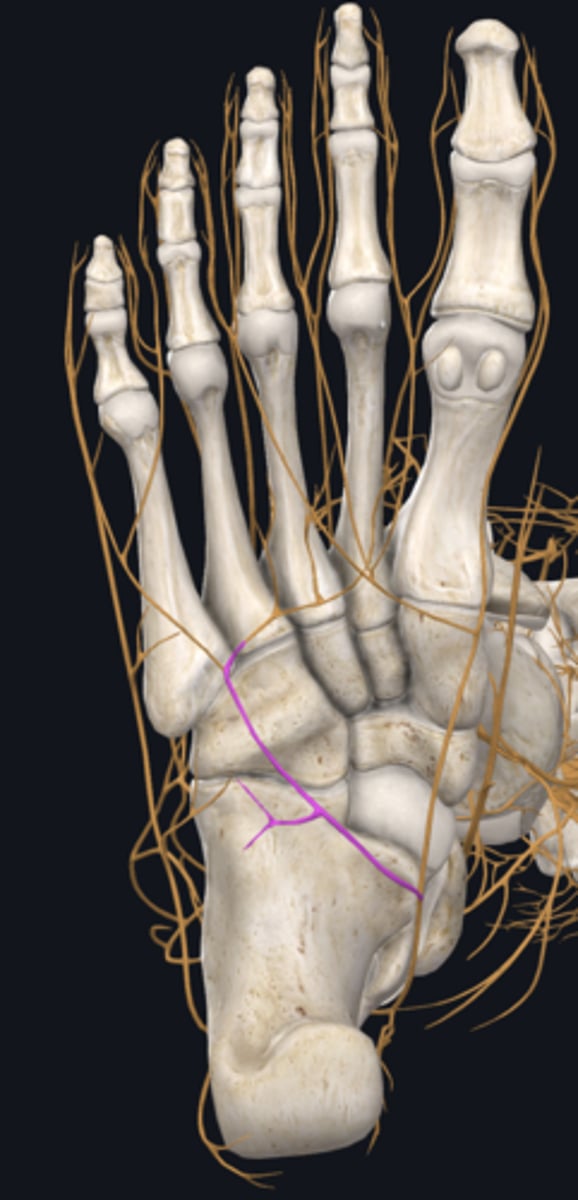

Common fibular nerve

nerve highlighted in pink

Deep fibular nerve

nerve, deep

Superficial fibular nerve

nerve, superficial

Dorsalis pedis artery

Superior extensor retinaculum

Inferior extensor retinaculum